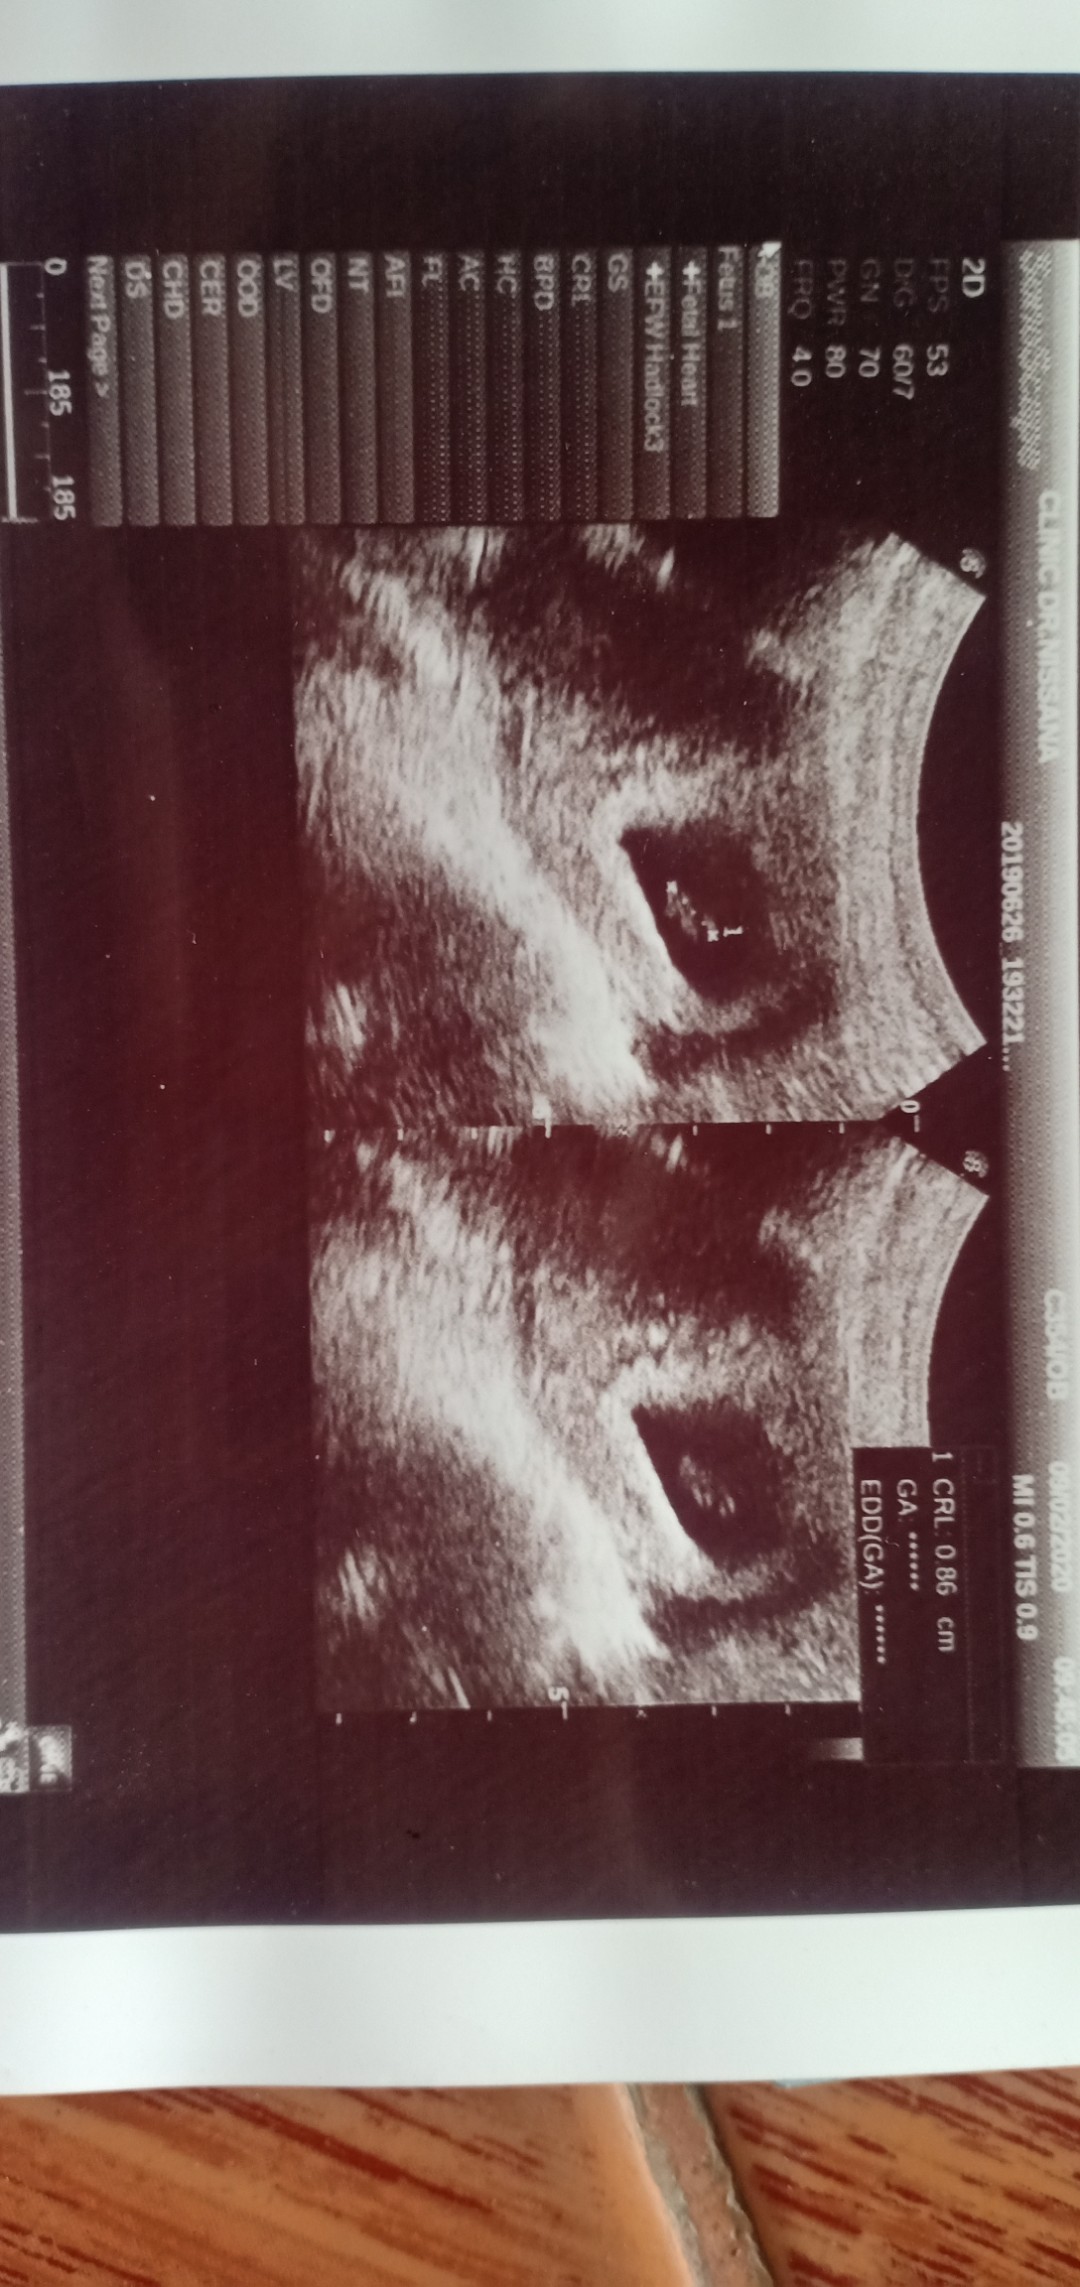

ยังไม่เจอตัวน้องเลยค่ะ ซาวด์ผ่านหน้าท้อง หมอโรงพยบาล 5w 4d หมออนามัย 7w 1d คุณเเม่เเอบกังวล